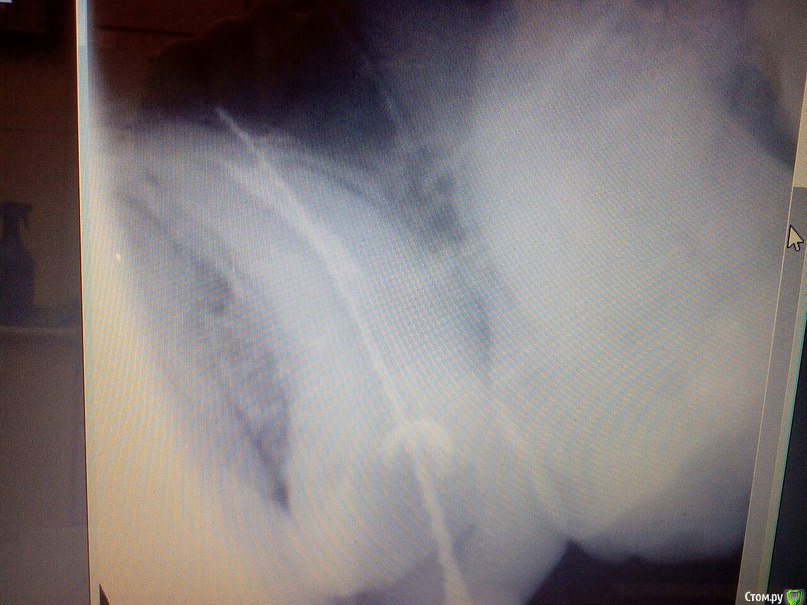

Kolchanov Опубликовано 28 июля, 2015 Поделиться Опубликовано 28 июля, 2015 Нет, что должен был бы я надеяться увидеть?Гуттаперчи в стенки вмазанной увидеть бы могли вы надеяться должны http://s017.radikal.ru/i412/1507/16/bb37360f0161.jpg Ссылка на комментарий